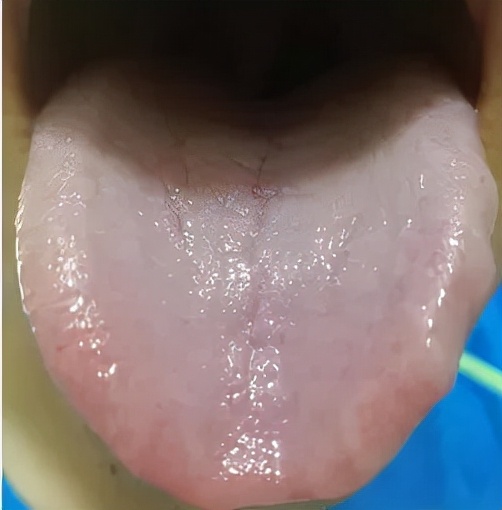

我看过很多气血不足的患者,他们的舌象都有一个非常明显的特征:舌质淡。

比如这个舌象:舌质淡嫩,舌边带齿痕,是气血亏虚,脾虚的表现。

脾为气血生化之源,脾虚则气血生化不足。

不能载血上充舌质,则舌质淡嫩。

脾虚运化水湿功能受阻,湿重压迫牙齿,久而久之形成齿痕舌。